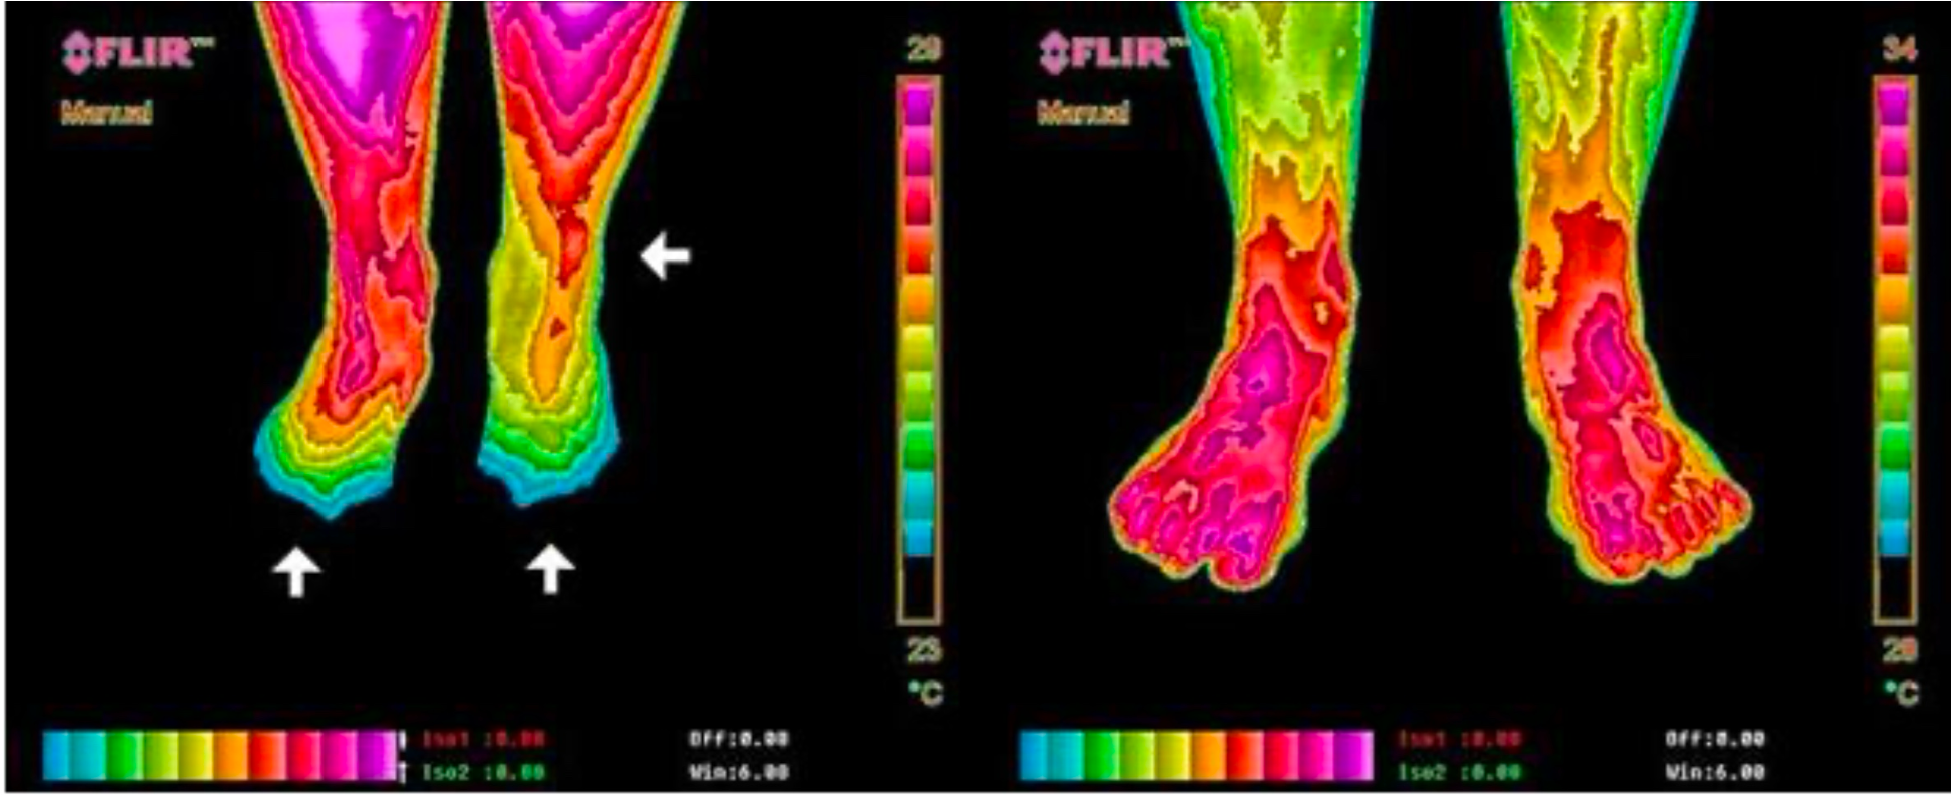

Análise de linha de base vs. Após 4 noites dormindo aterrado.

As áreas de maior calor (vermelho) indicam inflamação severa nas regiões de queixa do paciente. Após quatro noites utilizando um Earthing Sleep Mat, observa-se a resolução completa da inflamação e o retorno à simetria térmica normal.